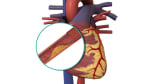

- Detect problems with blood vessels that affect blood flow. Examples of such problems include a tear in a blood vessel (which can cause blockage or internal bleeding), aneurysms (which are weaknesses in the blood vessel wall), and narrowed areas.

- Check how bad atherosclerosis is in the coronary arteries.

In some cases, a method called interventional radiology may be used during an angiogram to treat diseases. For example, a catheter can be used to open a blocked blood vessel, deliver medicine to a tumor, or stop intestinal bleeding caused by diverticular hemorrhage. To stop intestinal bleeding, the catheter is moved into the small artery where the bleeding is occurring, and medicine that narrows the artery or causes the blood to clot is injected through the catheter.